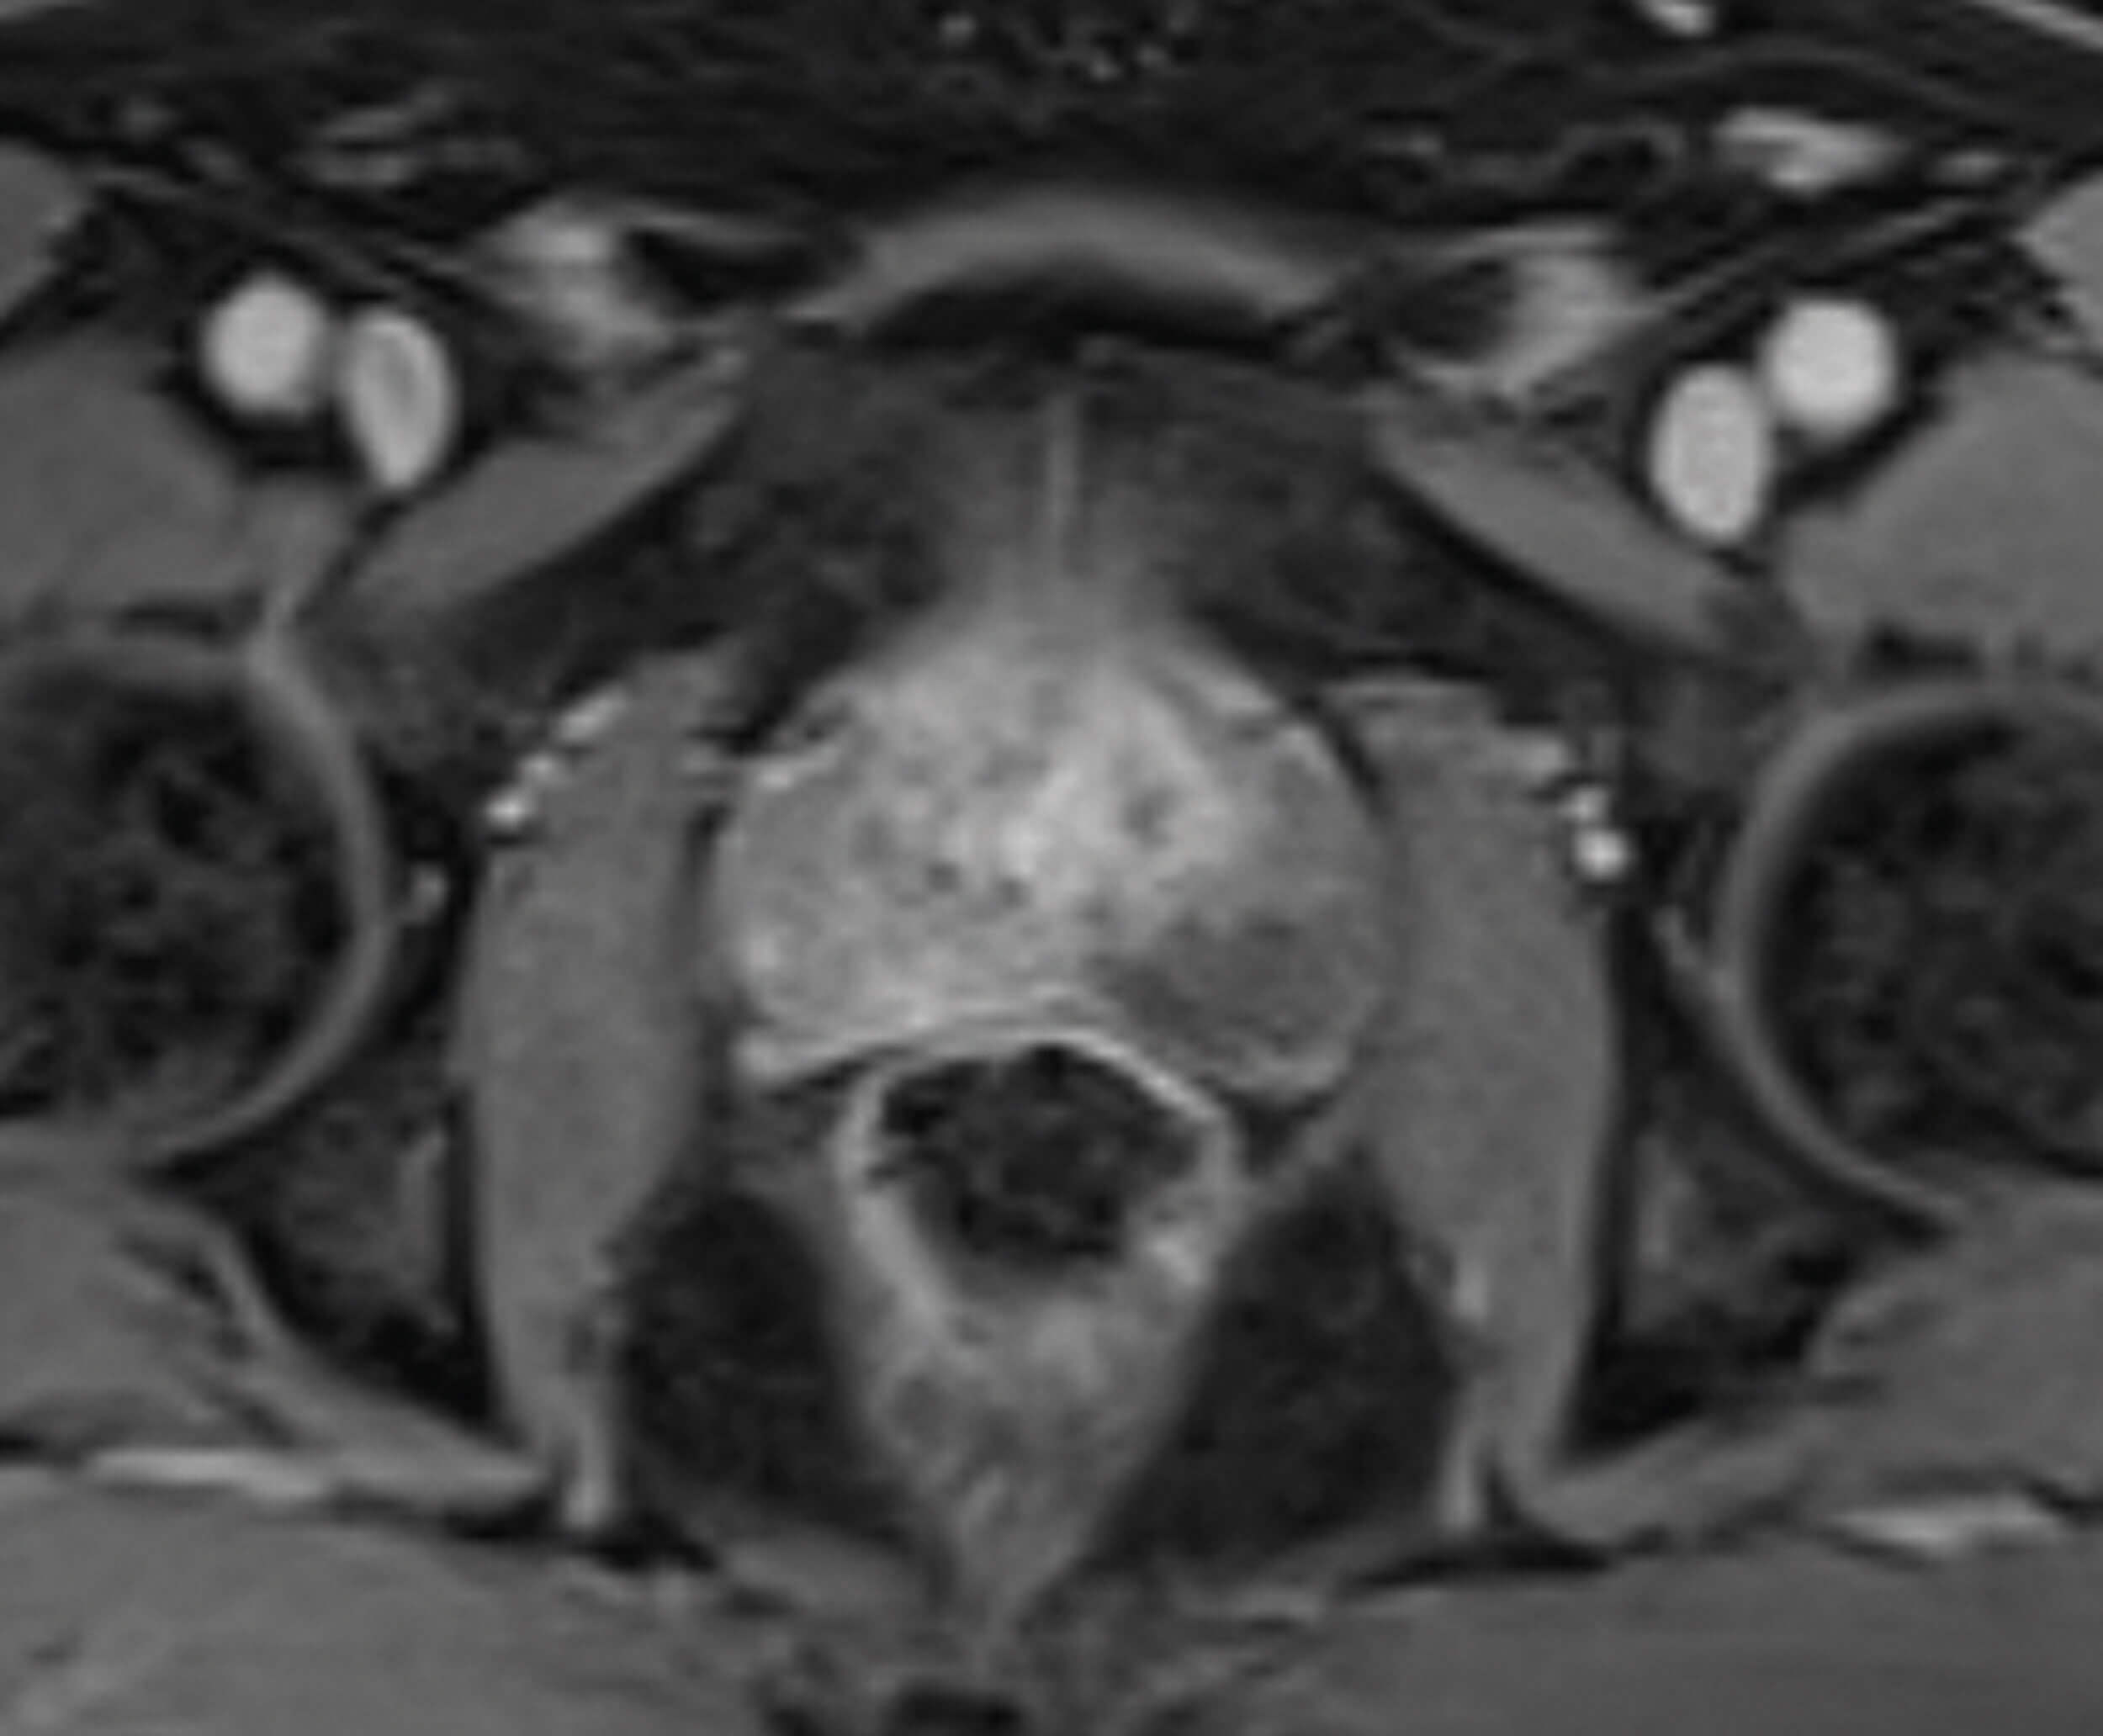

Figure 4.

Figure 4 is the dynamic contrast enhancement (DCE) sequence post injection of IV gadolinium. Tumour neogenesis causes contrast stasis in tumour regions and appear as enhancement. Prostate cancer therefore appears brighter on DCE, as seen in the right peripheral zone.